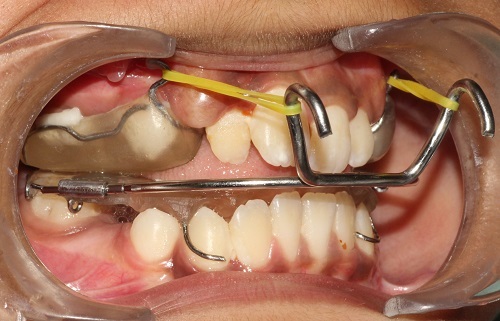

The various treatment offered in the department includes fixed orthodontic treatment with metal, ceramic,self-ligating brackets, treatment with mini-implants, Rapid Maxillary Expansion appliances, orthognathic surgeries to correct facial deformities, distraction osteogenesis procedures with Internal and External distractors, treatment of cleft lip and palate, Pre-surgical Naso Alveolar Moulding on cleft cases, Fixed functional treatment with Forsus, Powerscope, Herbst etc, Lingual Orthodontic treatment, Myofunctional Appliance Therapy, Aligner Orthodontic Treatment ,Myofunctional trainers, Splints- For Temporomandibular joint disorders as well as Class III correctors in growing individuals with appliances such as Tandem Traction Bow Appliance.